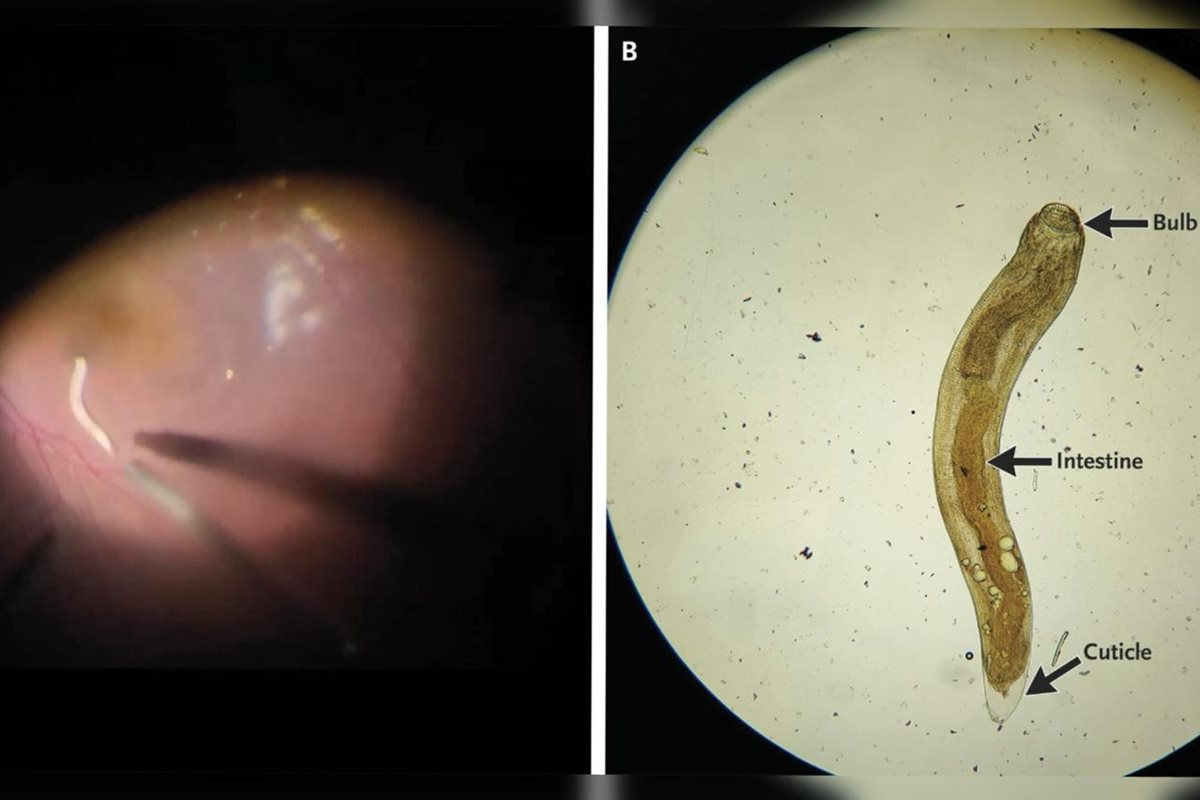

Foto em alta definição do verme encontrado no olho do paciente. Ao lado, uma ilustração do corpo do parasita

O globo ocular estava avermelhado, a pupila dilatada e fixa, e a precisão visual havia caído para 20/80. Durante o exame detalhado, os médicos identificaram o parasita se movendo no chamado “segmento posterior” — a parte interna e mais profunda do olho.

Para salvar a visão do paciente, foi realizada uma cirurgia chamada vitrectomia pars plana, que retira o humor vítreo (substância gelatinosa dentro do olho) e permitiu a retirada do verme.